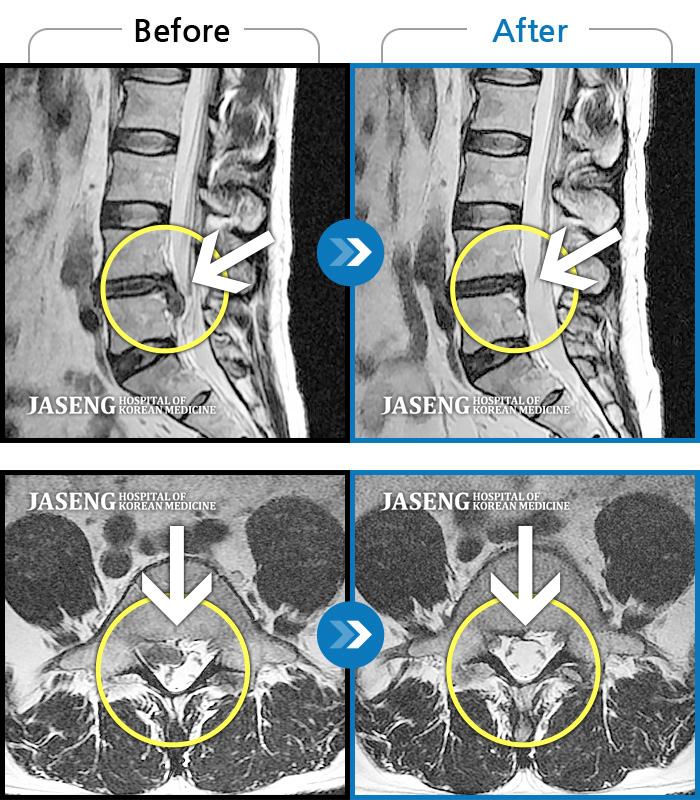

허리디스크

일산 · 김태용 원장

허리와 좌측 다리가 당겨 보행이 불가능했다.

촬영시기

2020.02.10 ~ 2021.02.22

2021.02.26